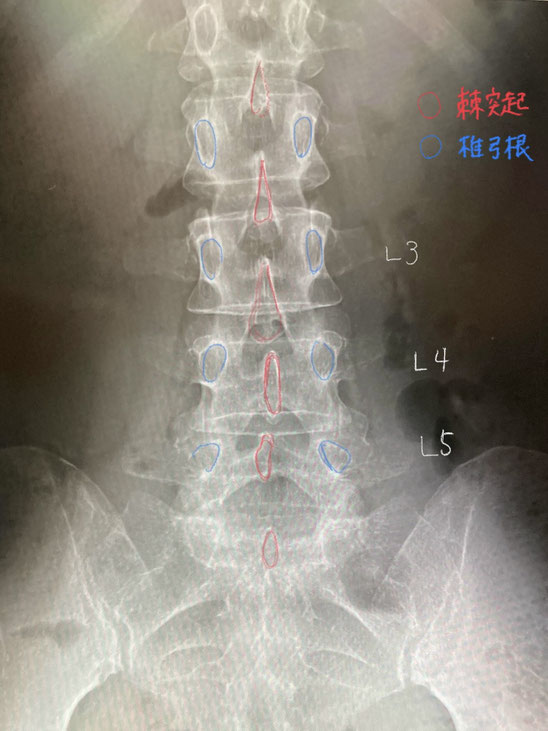

L5の棘突起(あか)は左に偏位しているように見えますが、これは「ずれ」ではなく、棘突起の個体差によるものと考えられます。なお、椎弓根(あお)の並びは正常。